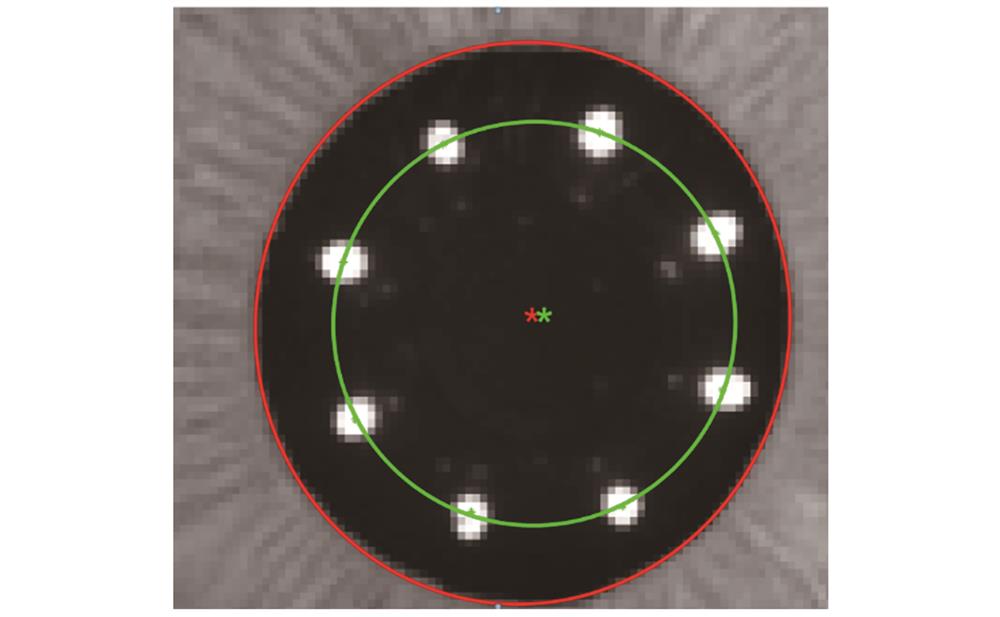

在得到瞳孔中心和光轴的图像坐标后,计算两者之间的相互关系,再通过位移台X和Y方向的移动,使得瞳孔中心与光轴重合,实现瞳孔对准。瞳孔中心与光轴相对位置的示意图如

图 8. 瞳孔中心与光轴相对位置示意图

Fig. 8. Schematic diagram of relative position of pupil center and optical axis